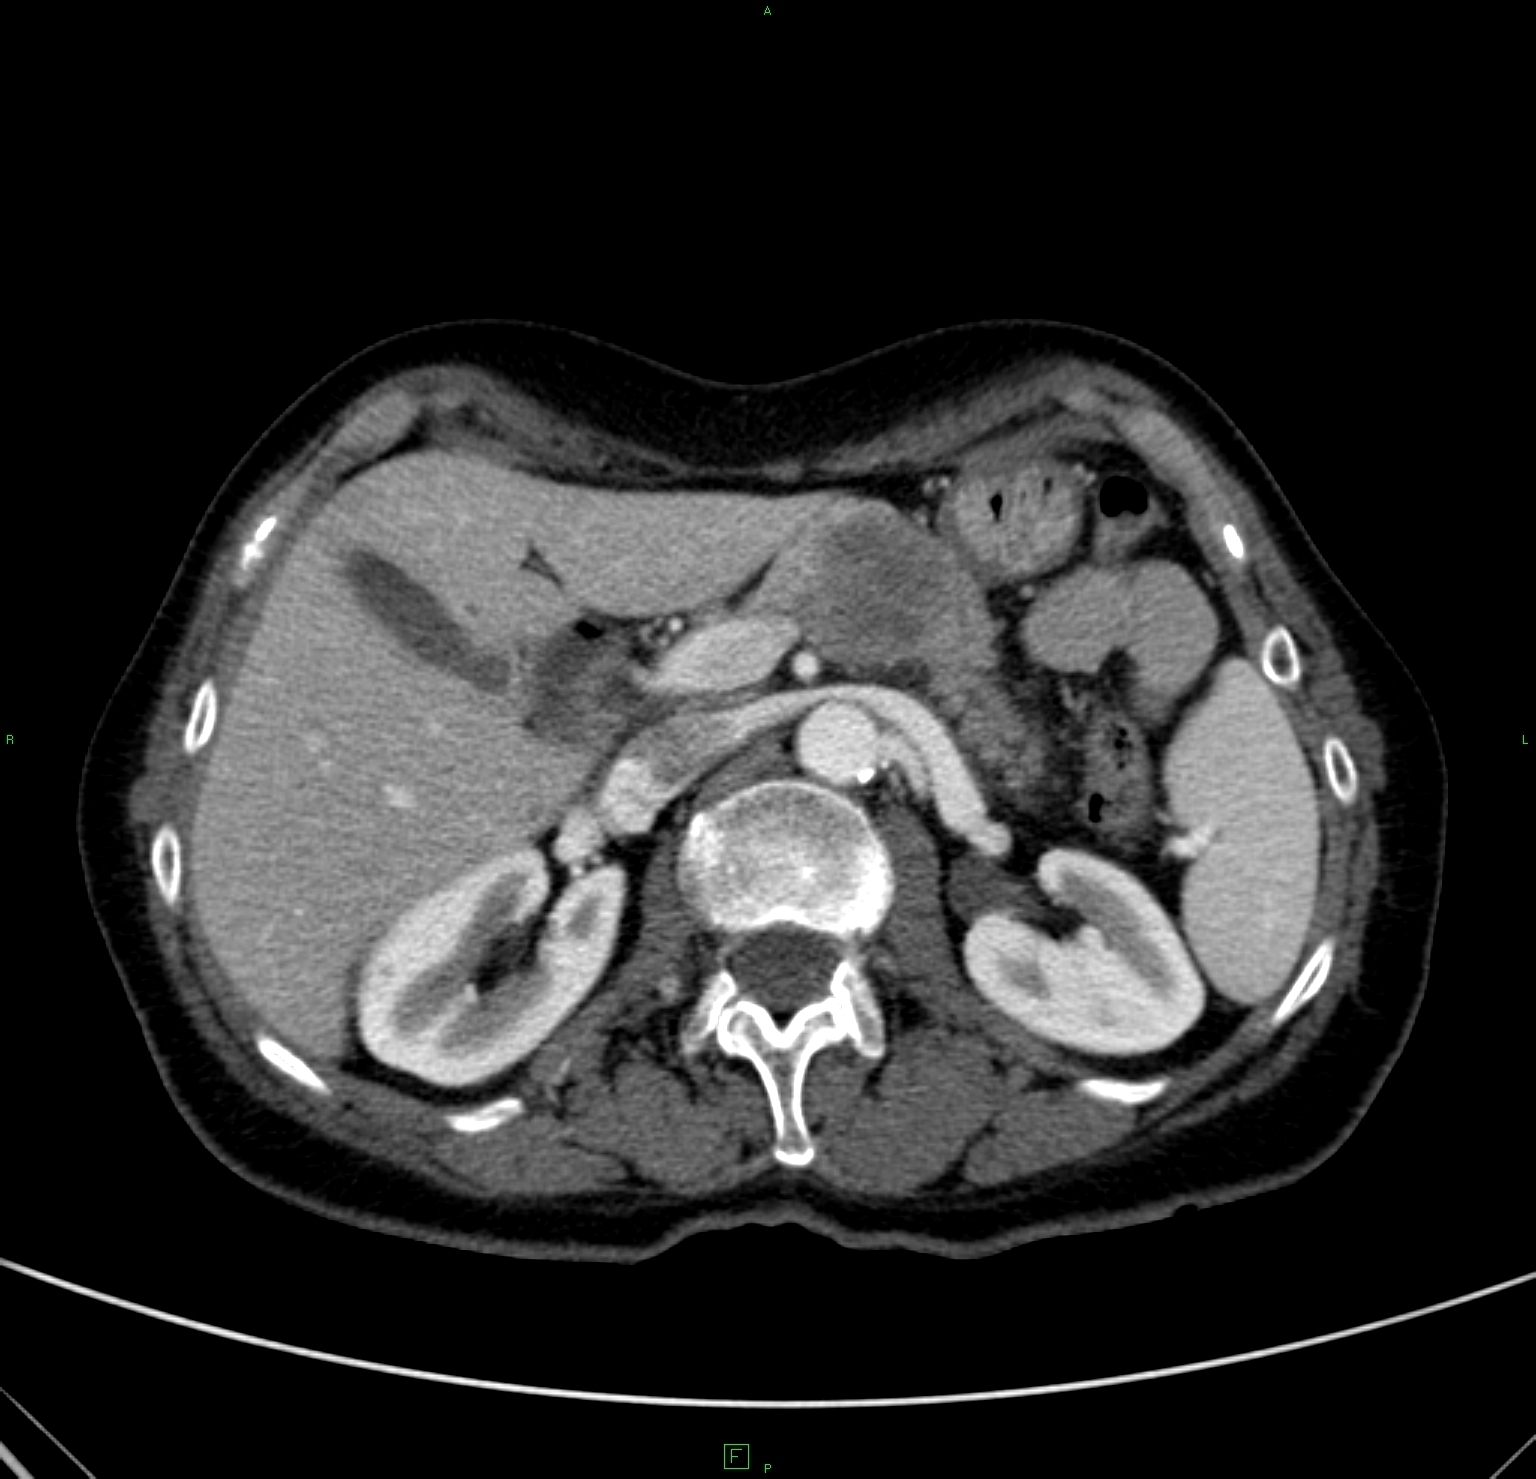

Nowadays, CT is a basically important method amongst the modern diagnostic imaging services. (Figure 4) By the application of the multidetector CTs a chance is given to perform multiphase (without contrast, arterial, portal and late phase) CT scans, which provide important additional information because of the different hemodynamics of certain intrahepatic nodules. Multiplanar (sagittal, coronal, oblique) and 3D reconstructions can be adopted from the axial plane CT slices. Due to CT angiographic techniques, excellent spatial resolutional 3D reconstructional images can be performed both on the arterial (hepatic artery) and the venous sides (portal vein, hepatic veins, collateral veins in case of portal hypertension, CT control of transjugular portosystemic shunts)..

Figure 4. Liver, contrast enhanced CT, venous phase